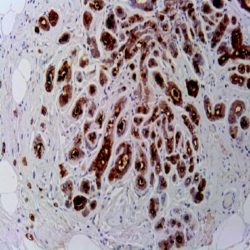

آنتی بادی P53  برند NOVOCELL یک ابزار تشخیصی پیشرفته برای شناسایی پروتئین سرکوب‌ گر تومور P53 طراحی شده است. این آنتی‌ بادی مونوکلونال با طراحی اختصاصی، قادر به تشخیص دقیق انواع جهش‌ های پروتئین P53 در نمونه‌ های بافتی پارافینی است. P53 به عنوان "نگهبان ژنوم" شناخته می‌ شود که نقش حیاتی در پیشگیری از سرطان از طریق مکانیسم‌ های مختلف از جمله توقف چرخه سلولی، ترمیم DNA و آپوپتوز ایفا می‌ کند. بیان غیرطبیعی یا جهش در این پروتئین در بیش از ۵۰٪ انواع سرطان‌ ها مشاهده می‌ شود. این آنتی‌ بادی با ایجاد رنگ‌ آمیزی هسته‌ ای واضح، امکان ارزیابی دقیق وضعیت P53 را در سلول‌ های سرطانی فراهم می‌ سازد.

• کلون‌های اختصاصی: طراحی شده برای شناسایی دقیق اپی‌ توپ‌ های پروتئین P53 انسانی

• عملکرد ایده‌ آل: رنگ‌ آمیزی هسته‌ ای واضح و مشخص در نمونه‌ های پارافینی

Novocell P53 antibody provides precise nuclear staining for tumor suppressor protein detection.